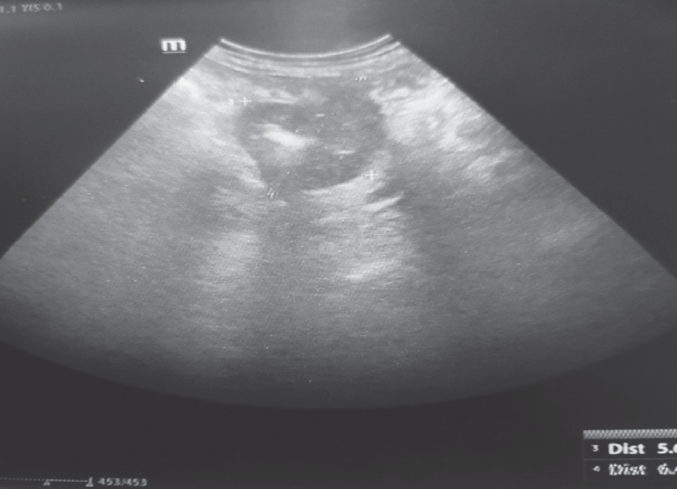

В случае сочетания ОКН с другими осложнениями при рентгенографии брюшной полости определялись признаки, соответствовавшие степени кишечной непроходимости. Ультразвуковое исследование выявляло свободную жидкость в брюшной полости, расширенные петли кишок с переполнением их содержимым при острой толстокишечной непроходимости. При ПФВ определялось утолщение стенок кишки с отеком прилежащих тканей (рис. 2).

Рис. 2. Ультразвуковое исследование. Опухоль сигмовидной кишки, осложненная перифокальным воспалением

Fig. 2. Ultrasound. Swelling of the sigmoid colon complicated by the development of perifocal inflammation